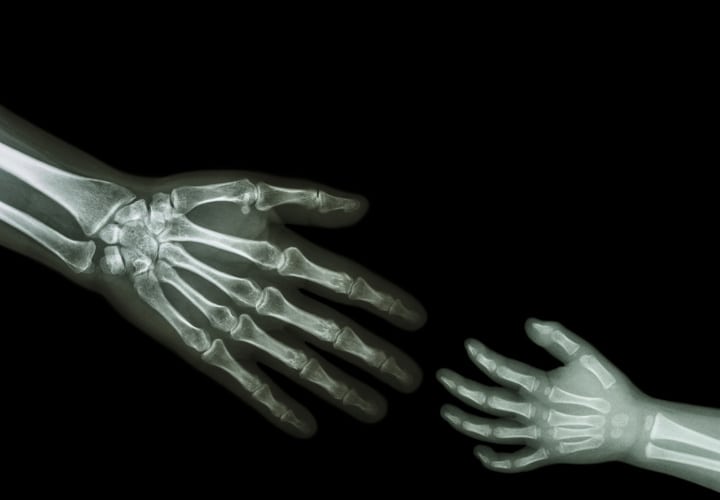

Al analizar a un bebé y compararlo con un adulto, nos podemos dar cuenta que los huesos no son ni del mismo tamaño ni tienen la misma elasticidad.

Cuando nacemos, si hiciéramos una radiografía notaríamos como los huesos no solamente se ven incompletos o aparentan espacios como si estuviera separado o “fracturado” alguno de los huesos; sino que podemos ver que “faltan” huesos.

Esto es porque para que el cuerpo se pueda ir desarrollando y vaya creciendo los cuerpos cuentan con un centro de crecimiento, generalmente en los extremos por donde el hueso va a ir creciendo y así alcanzar el tamaño adulto.